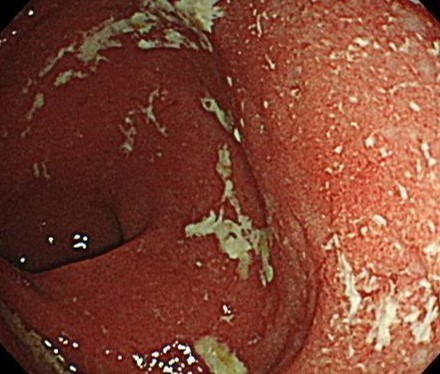

大腸内視鏡は、潰瘍性大腸炎やクローン病といった炎症性腸疾患の内視鏡診断にも非常に有用です。

潰瘍性大腸炎やクローン病も下痢や血便の原因の一つであり、症状や内視鏡検査などから総合的に診断し、治療を行います。